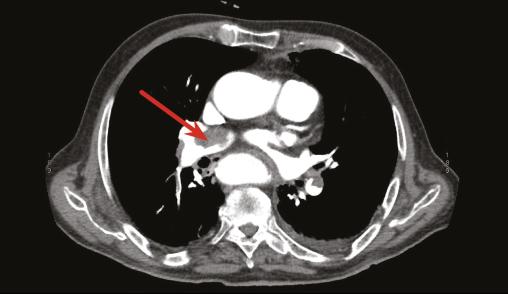

Un angioscanner thoracique objective une embolie pulmonaire bilatérale (fig. 1 ) et une échocardiographie transthoracique montre une masse d’échogénicité hétérogène polylobée mobile mesurant 30 mm, au niveau de l’oreillette droite attachée au septum interatrial (fig. 2 ). L’examen histologique confirme qu’il s’agit d’un thrombus (fig. 3 ). Face à ces résultats, l’indication chirurgicale est posée. Le patient est mis sous traitement anticoagulant, corticothérapie générale et immunosuppresseur.

L’échographie cardiaque permet de poser le diagnostic ; le myxome et la fibrose endomyocardique étant les diagnostics différentiels. L’angioscanner thoracique, voire l’imagerie par résonance magnétique cardiaque, peuvent aussi contribuer au diagnostic.1